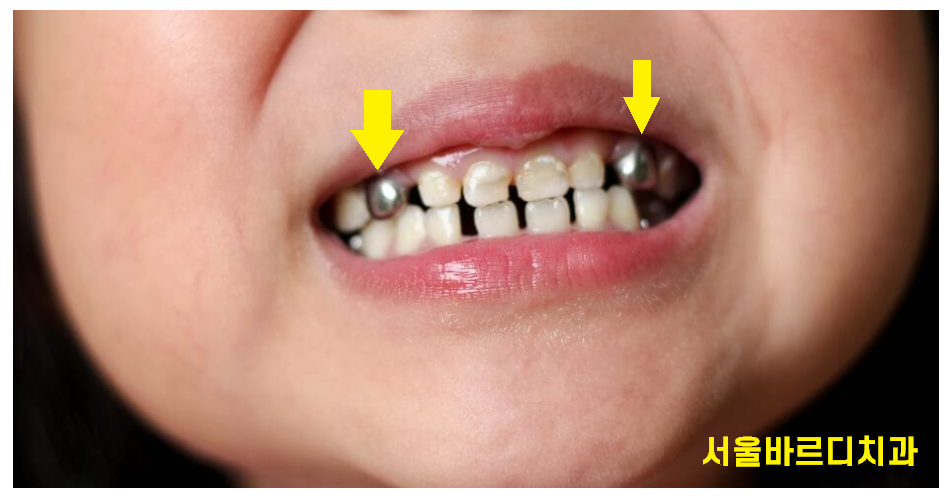

240809 염증이 심하여 유치 신경치료 후 은니를 씌워주었어요~!

ss crown이라 불리는데 어린이 전용 크라운이에요!

금니나 은니 색이라

빤짝거린답니다 ㅎㅎ